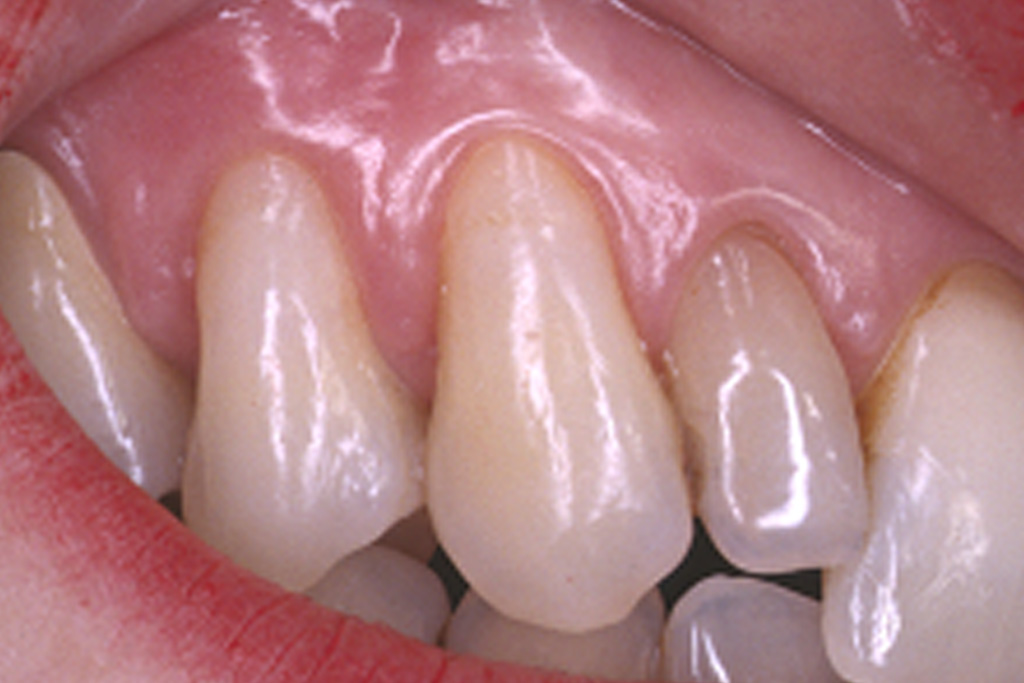

Die präzise Darstellung präparierter Zahnstümpfe auf dem zahntechnischen Meistermodell stellt auch heute noch eine der wichtigsten Schnittstellen zwischen Zahnarzt und Zahntechniker dar. In der Produktionskette hin zur fertigen Krone nimmt dabei der Zahnarzt eine entscheidende Schlüsselstellung ein. Nur er kann durch seine reproduzierbare und präzise Abformmethodik die Voraussetzung für ein perfektes Modell schaffen und damit Passungenauigkeiten der anzufertigenden Krone vermeiden. Dies ist besonders deshalb wichtig, weil Passungenauigkeiten an Kronenrestaurationen (Über- und Unterextension des Kronenrandes, übergroßer Randspalt ) häufig eine Fülle perioprothetischer und ästhetischer Probleme verursachen (Abb.1 ) :

Da die Präparationsgrenze bzw. der Präparationsrand in der Regel 0,5 bis 1,5 mm unterhalb des Zahnfleischrandes (= subgingival ) verläuft, wird zumeist während der Präparation des Zahnes das Zahnfleisch verletzt. In der Folge tritt eine verstärkte Blutung am Zahnfleischrand (= Sulkus) auf.

Bei der anschließenden Abformung der präparierten Zahnstümpfe bestehen zwei Probleme (Abb2.) . Zum Einen muss das den Zahn umgebende Weichgewebe vom Präparationsrand abgedrängt werden (= Retraktion) und zum Anderen darf während der Abformung kein Blut auf die abzuformende Zahnoberfläche gelangen. Unzureichende Retraktion und Blutungen im Sulkus verhindern eine präzise Abformung. Die Abformung muss wiederholt werden.

Mit Hilfe des Lasers können heute erstmals diese beiden. Hauptprobleme bestmöglich in den Griff bekommen werden.

Der Laser verdampft punktuell störende Gewebeanteile im Sulkus und stoppt gleichzeitig durch seine blutungsstillende Wirkung die Gewebeblutung . Dabei ist die Gewebeschädigung (=Trauma) minimal. Durch diese minimaltraumatisierende Wirkung ist die anschließende Wundheilung wesentlich schmerzärmer als bei der früher üblichen elektrochirurgischen Abtragung. Im Zuge der Heilung ist die Schrumpfungstendenz des Zahnfleischrandes zudem erheblich geringer. Dies fördert das ästhetische Erscheinungsbild der eingegliederten Krone im Zahnhalsbereich, da der Kronenrandbereich unterhalb des Zahnfleischrandes verbleibt (Abb. 3 ).

im Bereich der Vollkeramikkronen an den Oberkieferfrontzähnen 13-23